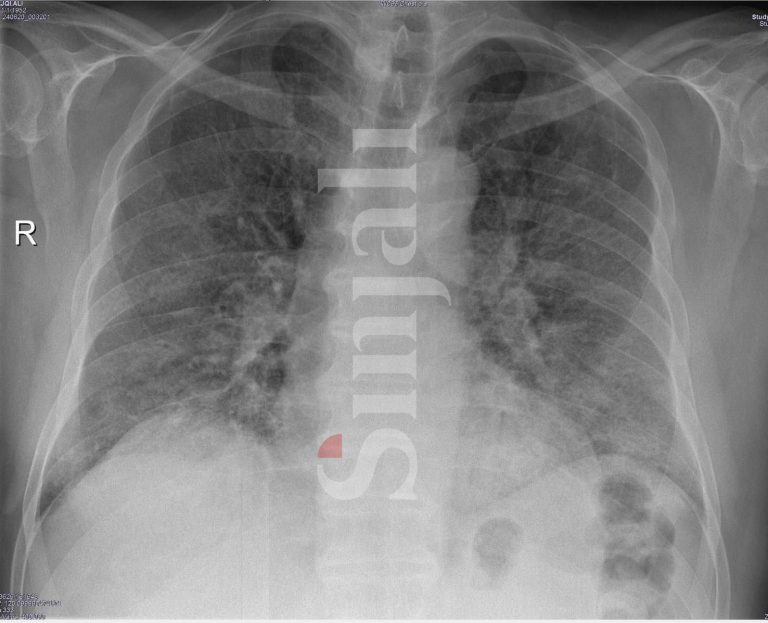

Gazeta Sinjali ka arritur t’i sigurojë Rentgenin e mushkërive të një 63-vjeçari, të cilat ishin të dëmtuara rëndë në më pak se 12 orë.

Fotografia e parë është në momentin kur është pranuar në spital, ndërsa fotografia e dytë është dëmtimi i mushkërive në më pak se 12 orë.